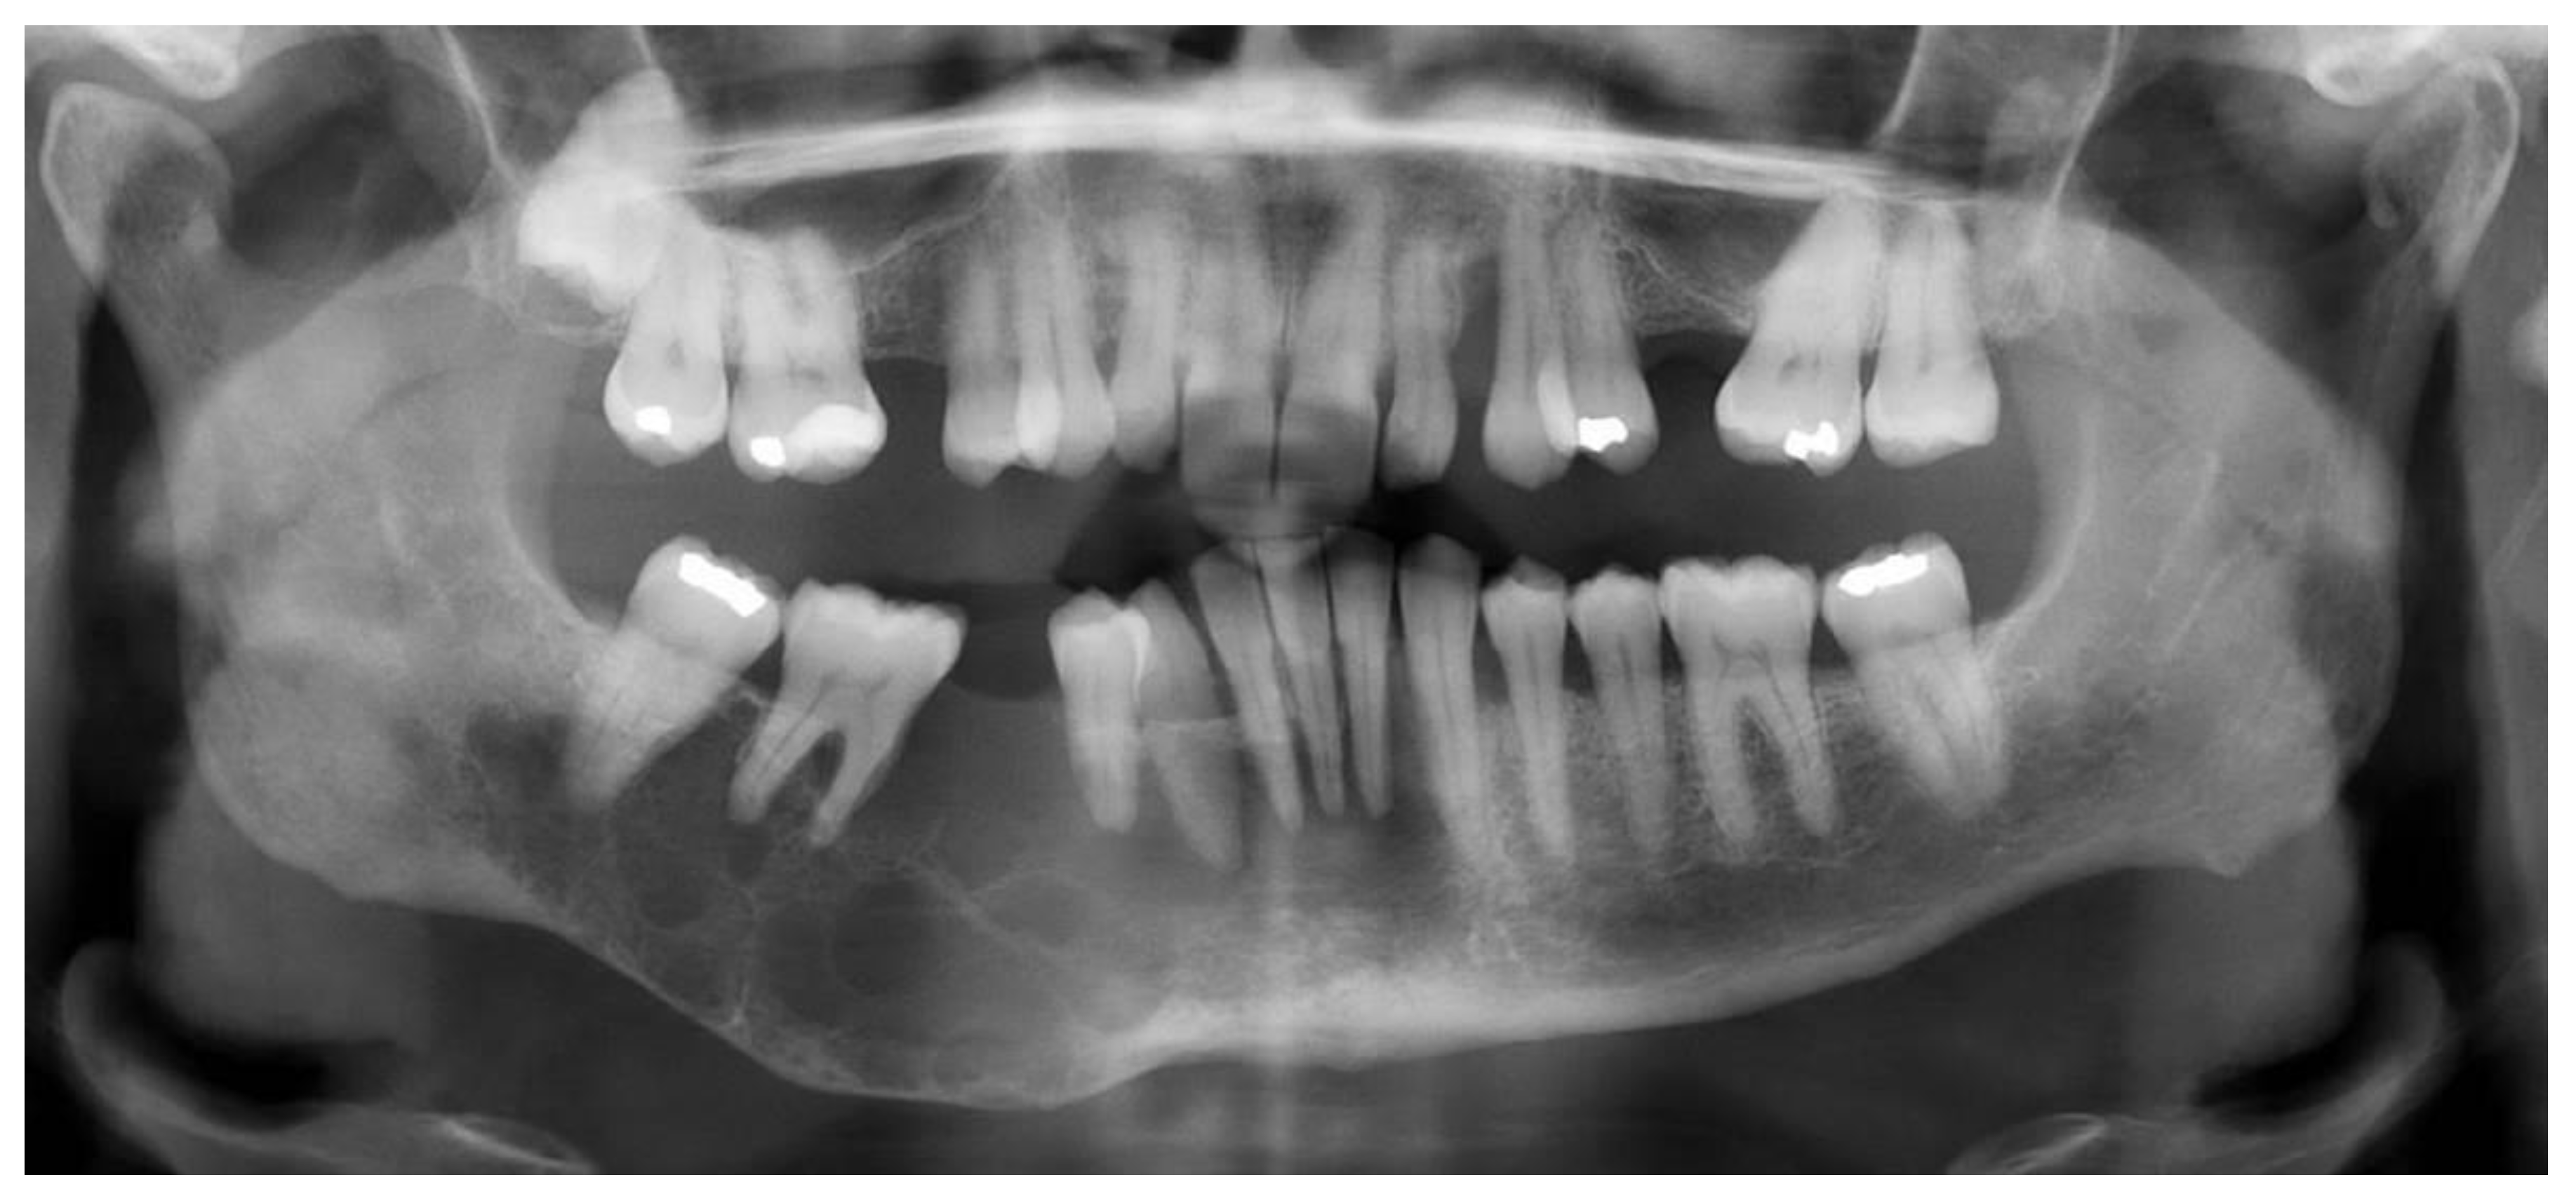

2.1. Case 1

2.2. Case 2

2.3. Case 3

| Age/Sex | 54-year-old female | 49-year-old female | 40-year-old male |

| Presentation | Painful mass | Painful mass | Mass recurrence |

| Location | Right maxilla | Right mandible | Right maxilla |

| Staining/IHC | PAS (+) D-labile Mucicarmine (−), p63 (+) CK5/6 (+), CK19 (+) | PAS (+) D-labile Mucicarmine (−) CK5/6 (+) | H&E only |

| Morphology | Infiltrative, non-encapsulated malignant neoplastic odontogenic epithelial proliferation with clear cell component in a dense fibrous connective tissue stroma. Neoplastic cells arranged in anastomosing trabeculae. Nuclear hyperchromasia and pleomorphism surrounded by clear, vacuolated cytoplasm. Stroma was hyalinized, densely collagenized, hypocellular, and hypovascular. | Neoplastic odontogenic epithelial proliferation diffusely infiltrated the connective tissue stroma. Neoplastic cells arranged in islands of variable size, trabeculae, and nests. Nuclei were hyperchromatic, central, and pleomorphic surrounded by clear cytoplasm. | Infiltrative odontogenic epithelial neoplasm intermixed with eosinophilic dentinoid matrix. Neoplastic cells arranged in infiltrative, non-encapsulated sheets, cords, and nests of polygonal cells with central hyperchromatic and slightly pleomorphic nuclei surrounded by clear cytoplasm and occasional pale eosinophilic cytoplasm. Occasional mitotic figures were noted. Neoplastic epithelial sheets and cords blended with eosinophilic cellular matrix without cellular rimming consistent with dentinoid deposits. |

| Procedure | Right maxillectomy with negative margins | Left mandibulectomy Right temporomandibular joint arthroplasty Left fibula free flap | Right maxillectomy without orbital exenteration Right selective neck dissection Forearm free flap Four months adjuvant radiation |